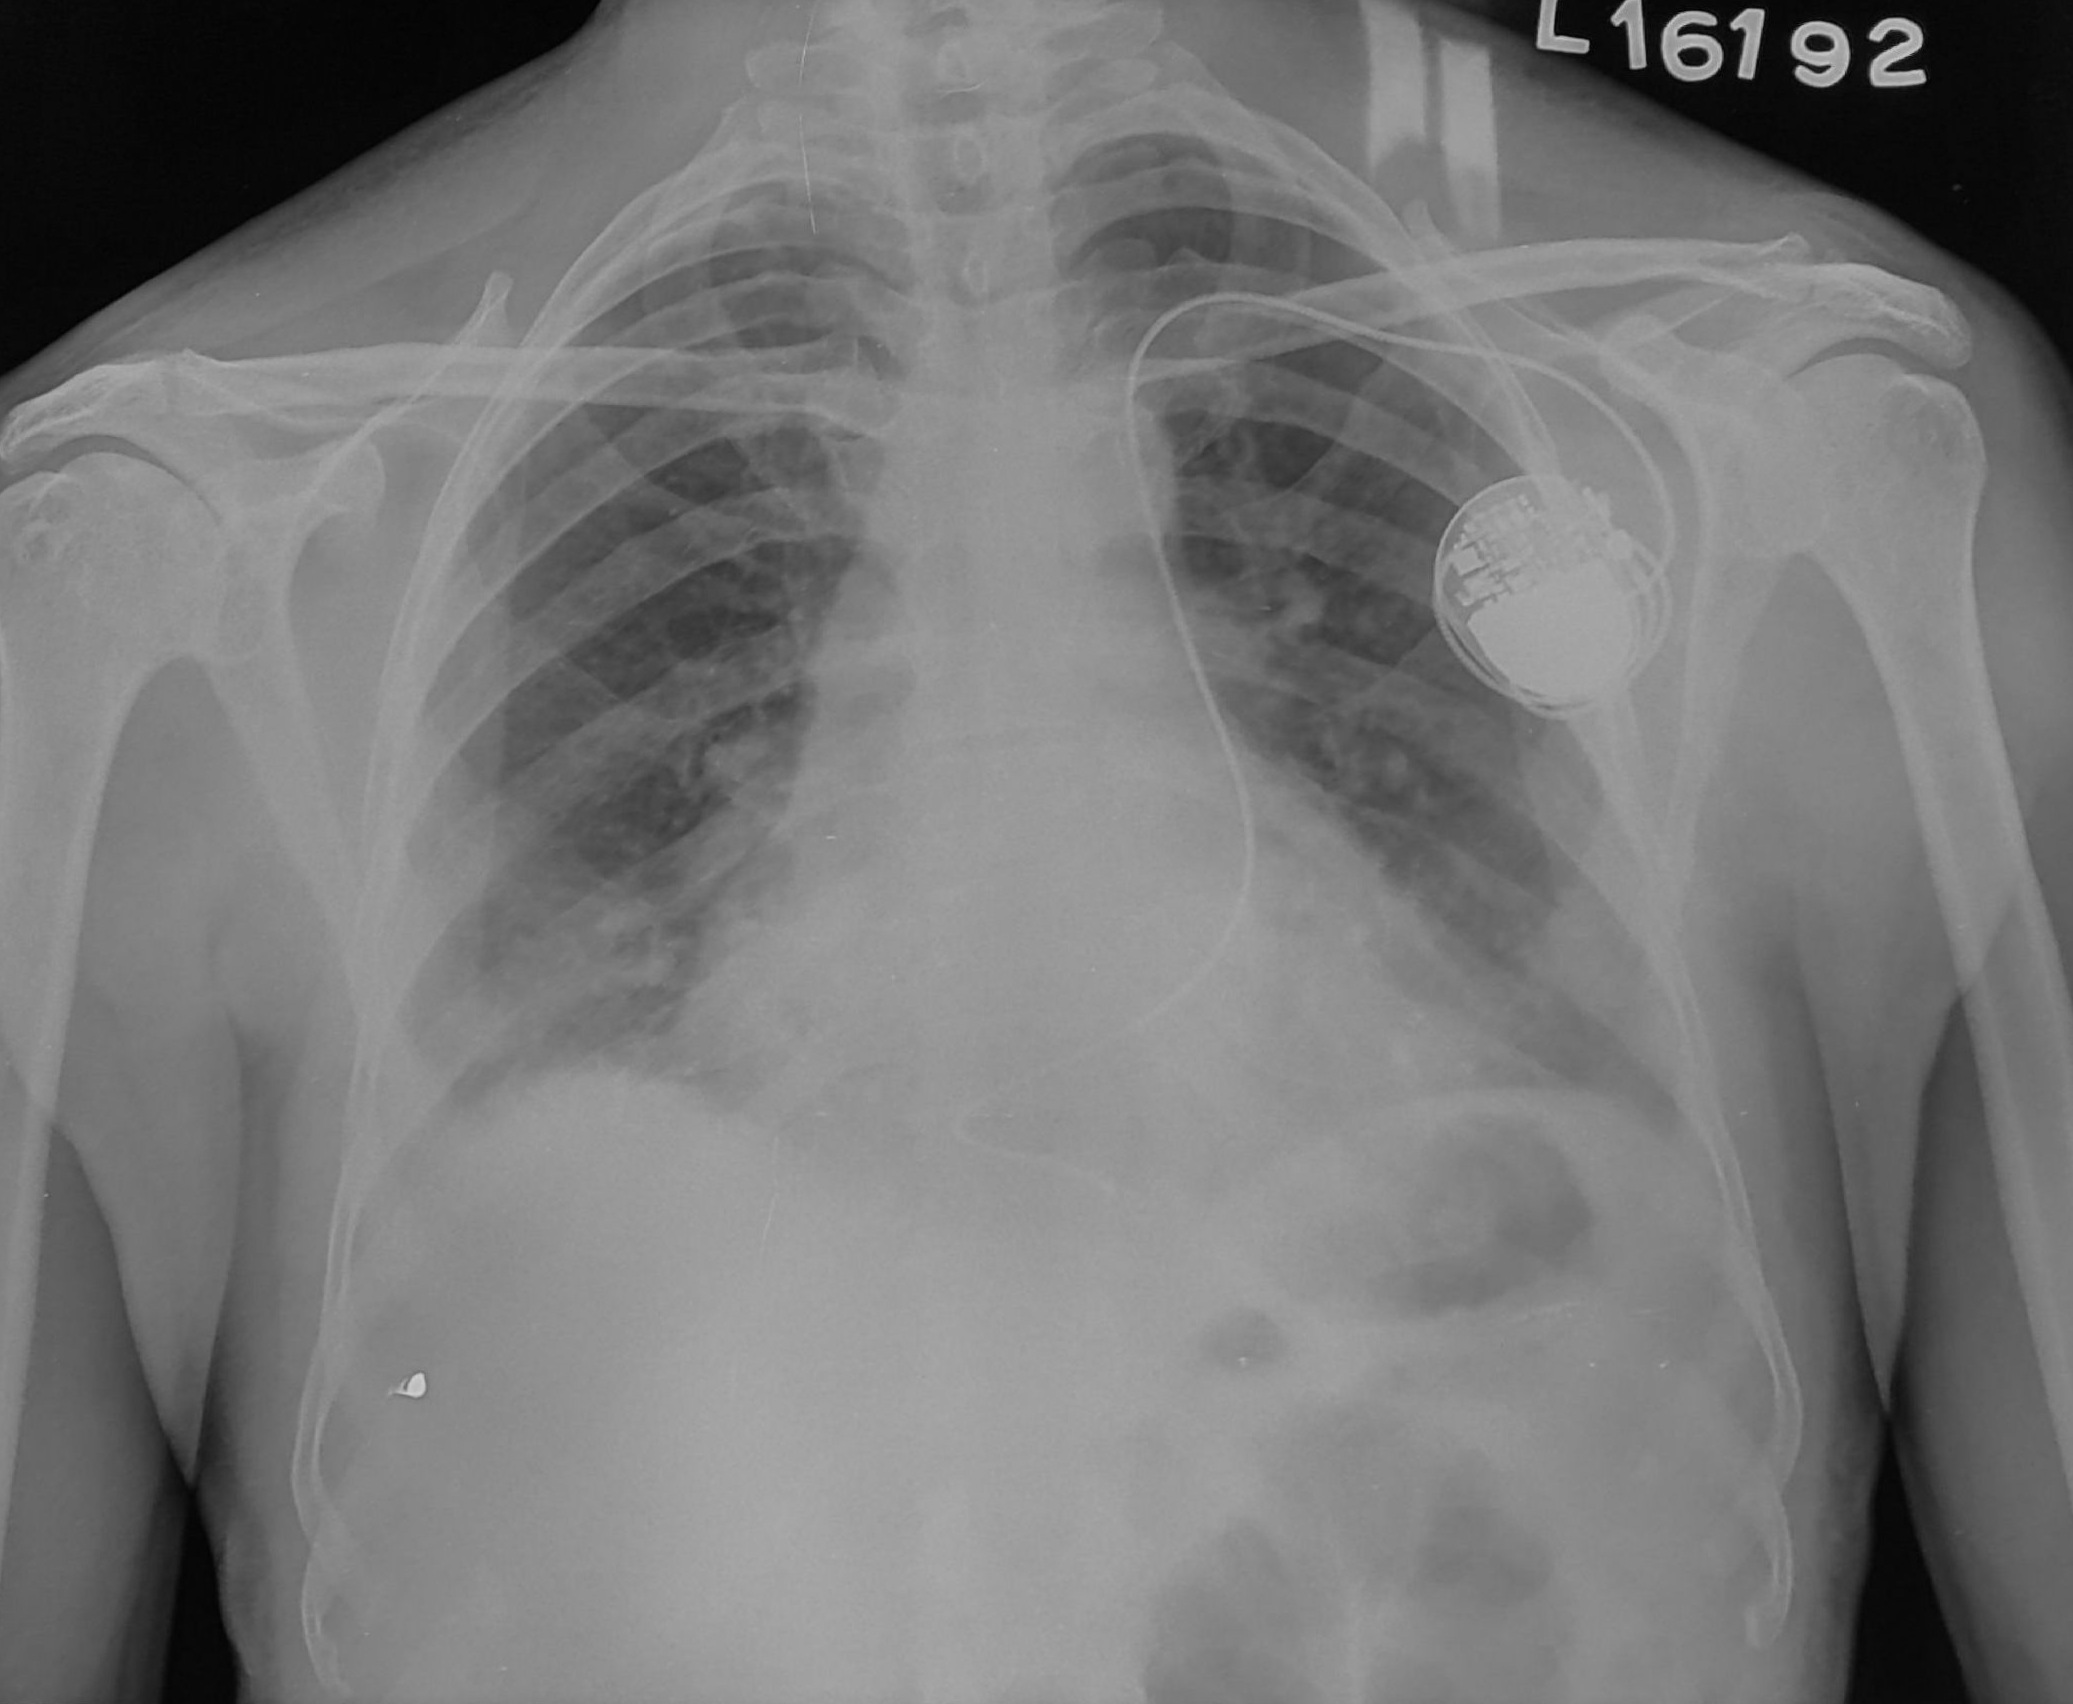

Post implant

• Chest X ray after 4-6 hours